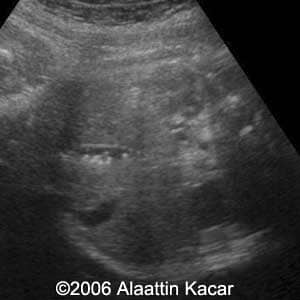

Gallstones Alaattin Kacar, MD Sureyya Paksoy MD Burhan Seker, MD Ender Birgul, MD Article Published: Jun 8, 2006 Balikesis, Turkey These are several images of a fetus with multiple gallstones Discussion Board Start a discussion about this article Add to Favorites Favorite